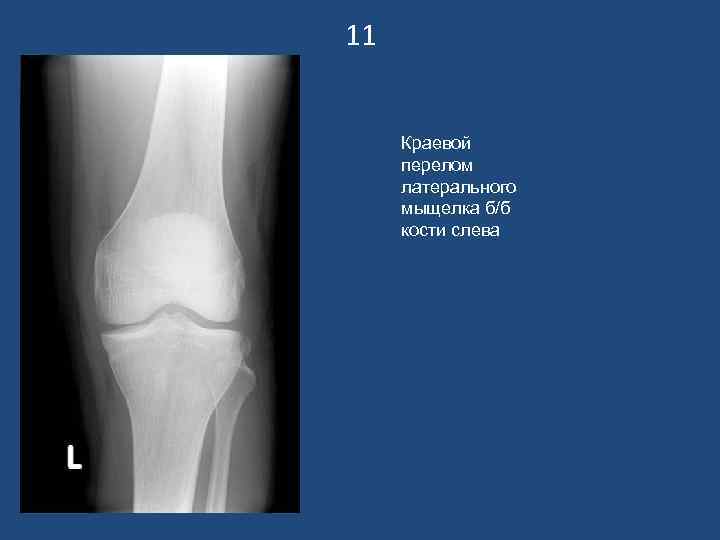

11 Краевой перелом латерального мыщелка б/б кости слева